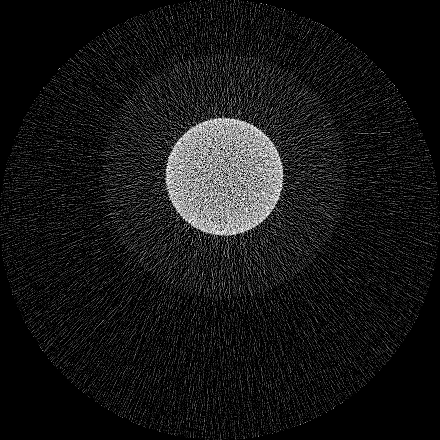

Figure 7 shows a single slice spectral reconstruction of the Mg scaffold. Due to low atomic number of Mg (Z = 12) compared to Ti (Z = 22), the results did not exhibit any significant beam hardening effects. Low energy reconstruction shows good spatial information while high energy ranges are limited by photon noise. In scans involving smaller samples made from low-Z materials like Al or Mg, acquiring low energy quanta in CSM provide high spatial information with minimum or no beam hardening effects. Figure 8 illustrates a single slice spectral reconstruction of the Ti mesh. Similar to the Ti scaffold, streaks are less pronounced in the mid and high energy ranges.

Refer to caption

(a) 15 to 80 keV

(b) 35 to 80 keV

(c) 55 to 80 keV

(d) 62 to 80 keV

Figure 8: Spectral reconstruction of Ti mesh sample. Minor streaks are visible in the low energy range.